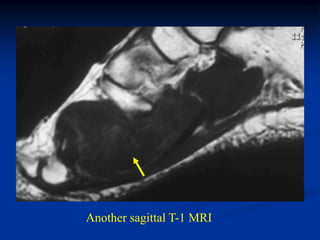

Case #1190.2 33 yearold female with painless lump at ankle for 1 year

• 72.

Sag T-1 PD Gad